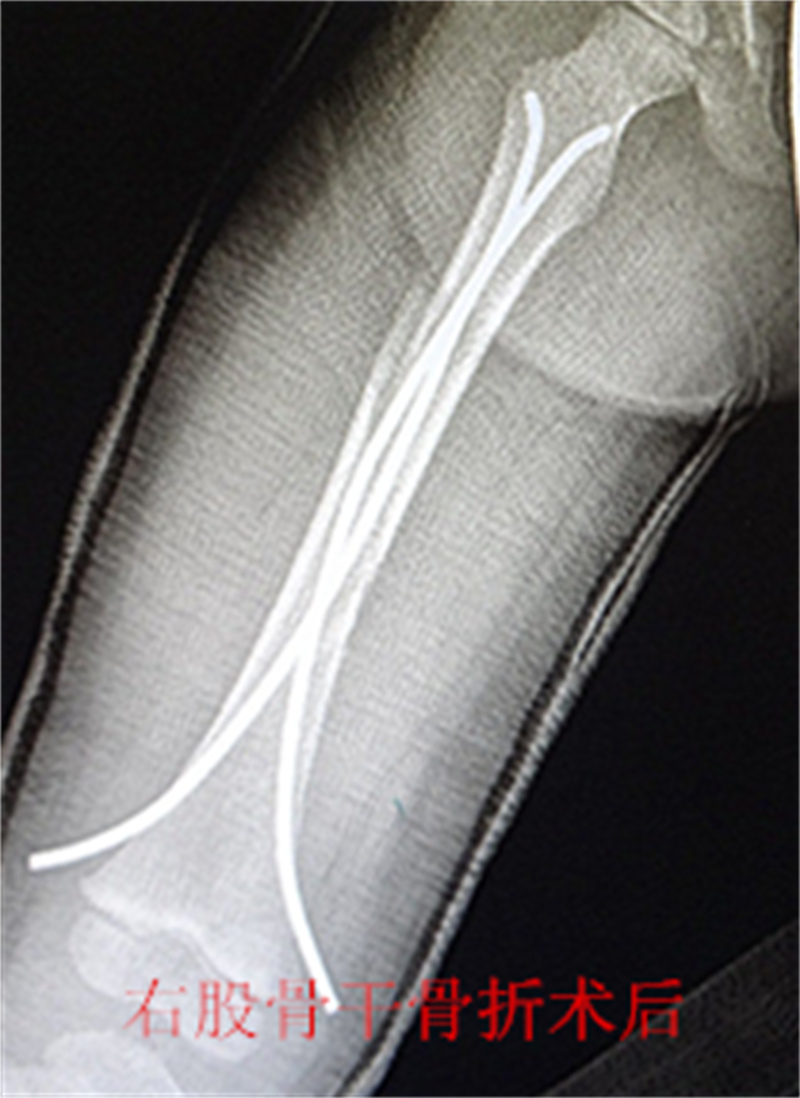

,弹性髓内钉内固定解决了这个矛盾。有人说,弹性髓内钉的出现是上天对儿童的恩惠。的确,弹性髓内钉是治疗小儿长管状骨骨骨折的一种理想、可靠的内固定方法。弹性髓内钉技术发源于法国,在欧洲广泛应用后,现已为全球所接受,被称为是儿童骨科界的一次革命。徐州儿童医院骨一科应用弹性髓内钉技术治疗四肢长管状骨骨折,具有创伤小、恢复快、并发症相对少,孩子能较快恢复正常生活、学习等优点。该技术先将骨折闭合复位,通过微小的切口将特制的弹性髓内钉置入骨髓腔,达到固定骨折的目的。适用于肱骨,股骨,尺桡骨等部位的常见骨折(图)。